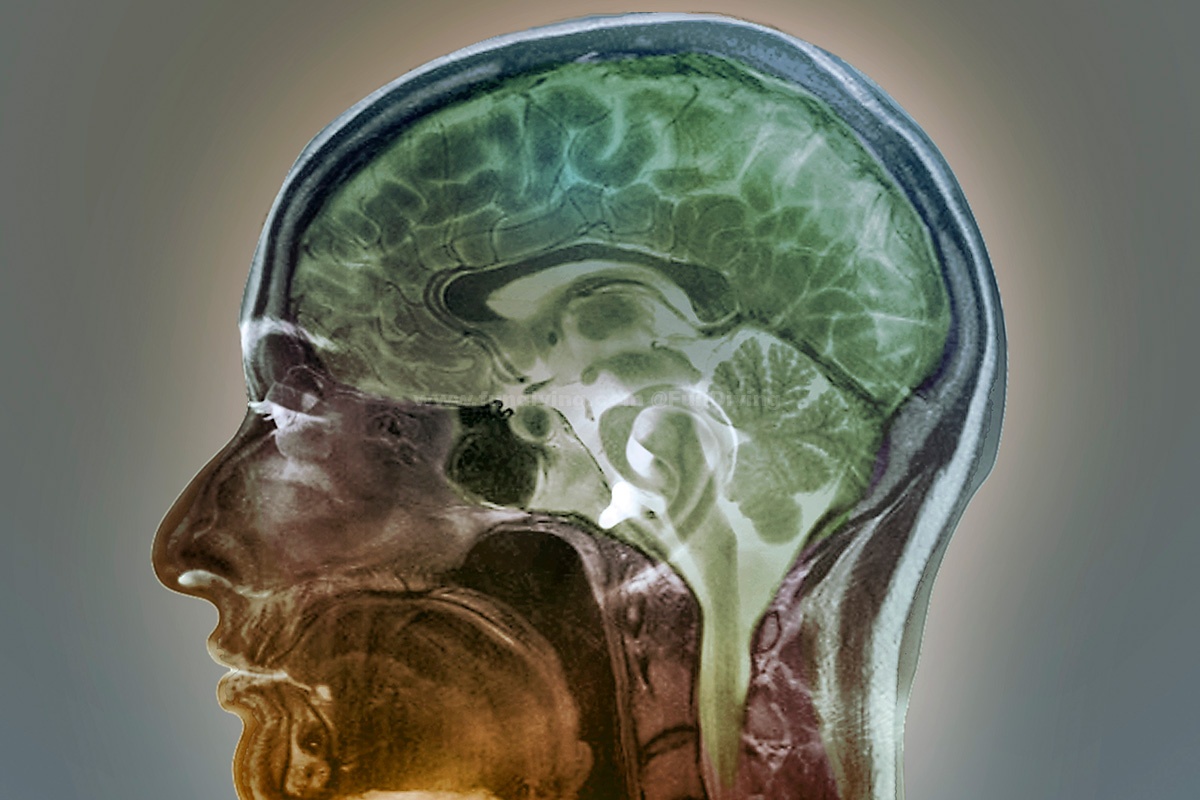

除了交流能力,它们的智商整体都很高,可以和灵长类齐平!(森森的危机感)它们的大脑和人类极为相似,有沟回,有分区,有皮层,还有海马区!(记忆力应该很好)